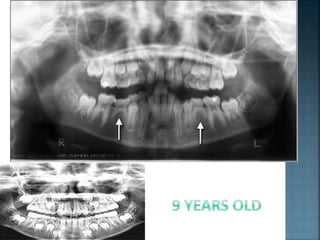

A nine-year-old girl was referred by her

dentist regarding both upper central

incisors, which were in crossbite. She

presented with a Class I incisor

relationship on a Skeletal I base in the

mixed dentition. The upper labial segment

was spaced with the lower being well

aligned. She had a premature contact on

the central incisors with a resultant 2 mm

anterior displacement on full closure.